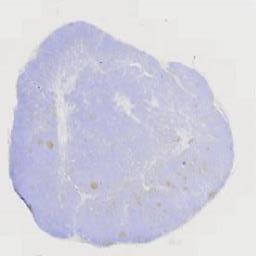

临床资料: 1.患者,女性,55岁,因"无意间发现腹壁肿物10天余"入院。2.腹部查体:双腹壁可触及约1.2*1.0cm大小肿物,质韧,边界清,活动度欠佳,有轻微疼痛不适,局部皮肤无红肿及破溃。3.既往史:有高血压病、糖尿病病史5年,口服降压、降糖药物,均控制尚可。2025年2月28日在我院行"右侧甲状腺癌根治术",现口服优甲乐,定期复查。既往有"梅毒"病史,经正规治疗后,现已治愈。4.我院彩超显示:左侧前腹壁实性占位,右侧前腹壁实性占位,较大者位于左上腹壁,大小约2.1cm*1.4cm。

大体所见: (腹壁肿物)淡黄不整形组织一块,大小为2.2*1.4*1cm,切面灰黄,质中。

免疫组化: 阳性表达:S100、CD68、CyclinD1、Lambda、Kappa。MUM1.阴性表达:CD34、SMA、ALK(5A4)、CD1a。其他:Ki67(+,约5%),P53(+,野生型)。